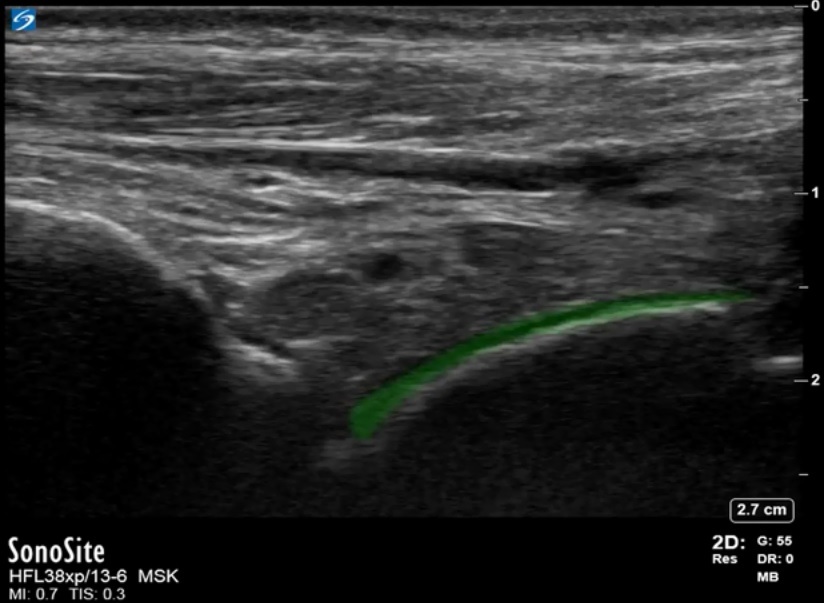

Foot & Ankle Anterior Recess Hyaline Cartilage Image

Highlighted Area: Hyaline Cartilage